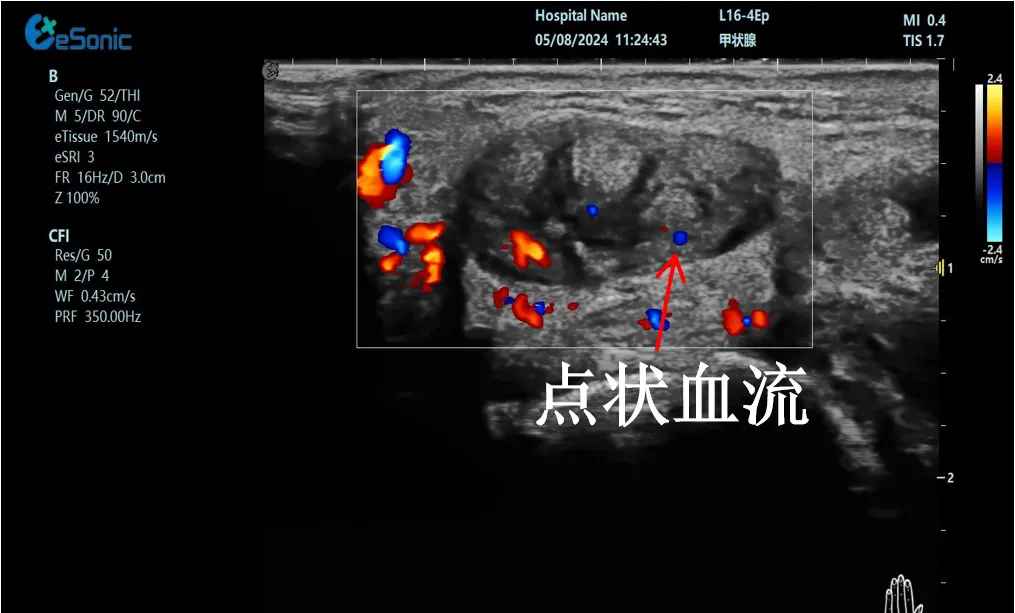

mFlow?技术在腱鞘炎诊疗中的应用

【背景】:左手腕关节第四腔室腱鞘炎。

【痛点】:普通彩色多普勒不敏感,只能看到细小点状血流,容易被忽略,难以进行分级诊断和疗效评估。

【方案】:hjc888黄金城官网医疗(ESI)超微血流技术可以看到腔室内肌腱周围环状血流,可充分提示:

1、处于炎症活动期;

2、根据血流进行分级诊断提示1级;

3、治疗后根据血流多少评估疗效(见右下图:治疗10天后复查超声,微血流图像血供消失)。